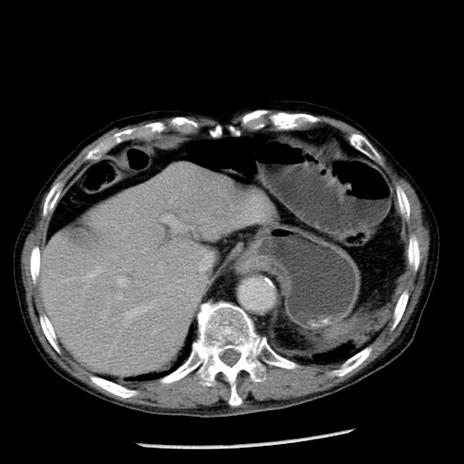

冠状断像

症例26(横断像)

【症例】80歳代男性

【主訴】嘔吐

【現病歴】昨晩2回嘔吐あり、今朝になっても嘔吐あり。来院。

【既往歴】胃潰瘍

【身体所見】意識清明、BT 37.6℃、BP 166/95mmHg、HR 100bpm、SpO2 97%、腹部:平坦・軟、腸蠕動音聴取良好、圧痛なし。

【データ】WBC 21900、CRP 1.46